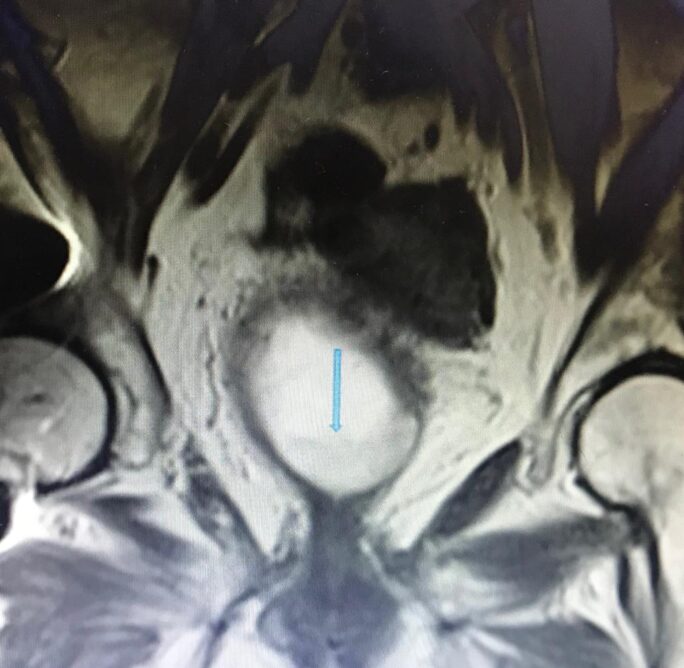

RM Biparamétrica de vejiga. (Cáncer de vejiga)

Femenina de 80 años, con prótesis en cadera derecha. Antecedente de IRC. No es posible realizar estudio de angiogénesis, por presentar TFG de 15ml/min y por consiguiente no administramos contraste endovenoso. Sin embargo, con las secuencias morfológicas y funcionales de la RM, es posible hacer el diagnóstico y el estudio de extensión de la lesión. ( T2 N0 M0. Estadio II). La Difusión -RM, nos permite determinar la celularidad tumoral y eventualmente monitorear la respuesta al tratamiento.